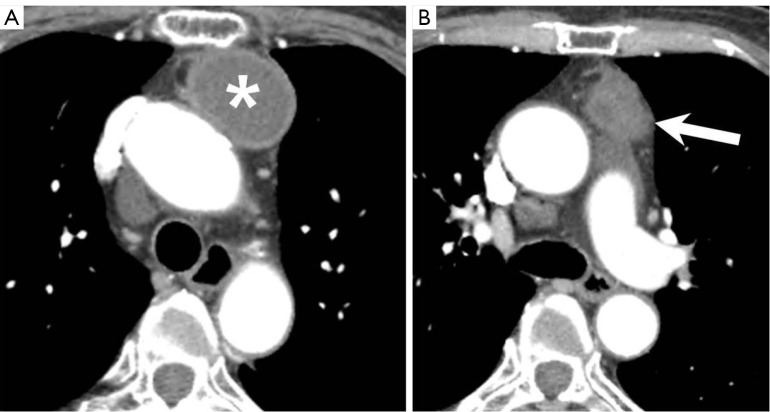

Case description: A 60-year-old woman visited Inje University Sanggye Paik Hospital with left hilar bulging detected on routine chest radiograph. A chest computed tomography (CT) scan revealed a 6 cm well-defined cystic mass with partial septation in the prevascular mediastinum. Thus, secondary thymic cyst was suggested. On the follow-up chest CT scan taken 3 months later, the size of the thymic cyst decreased, while the solid portion increased slightly, suggesting the potential presence of malignancy. Consequently, surgery was conducted. Adhesion to the lung and aorta was observed, but they were relatively well separated. The pathological findings revealed a partially ruptured thymic cyst with fat necrosis and multifocal granulomas.